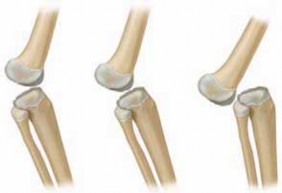

Chapter 21 Proximal Patellar Realignment Jay C. Albright DEFINITION Instability of the patellofemoral joint i…